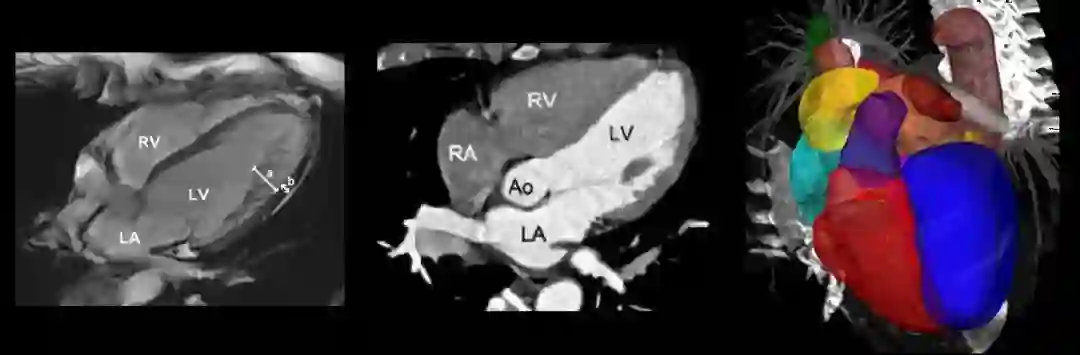

在心脏分割问题中,通常按结构将心脏分成几个标注区域。比如以MM-WHS数据库为例,有:

• 左心室血腔(the left ventricle blood cavity, LV)

• 左心室心肌(the myocardium of the left ventricle, Myo)

• 右心室血腔(the right ventricle blood cavity, RV)

• 左心房血腔(the left atrium blood cavity, LA)

• 右心房血腔(te right atrium blood cavity, RA)

• 升主动脉(the ascending aorta, AA)

• 肺动脉(the pulmonary artery, PA)

这些区域由于本身的特性,其难易程度和分割手段也存在不同。通常来讲,普适性的心脏分割算法能够实现基本的区域分割,但是要实现精准分割还是需要对单独区域进行单独处理。相对而言,右心室(RV)的分割难度更大,我们就以此为例分析一下其存在的难点。

2. 完整心脏分割

基于P3D和FPN实现完整的心脏分割:

Zhanwei X., Ziyi W., and Jianjiang F.. CFUN: Combining Faster R-CNN and U-net Network for Efficient Whole Heart Segmentation[C]. CVPR 2018.